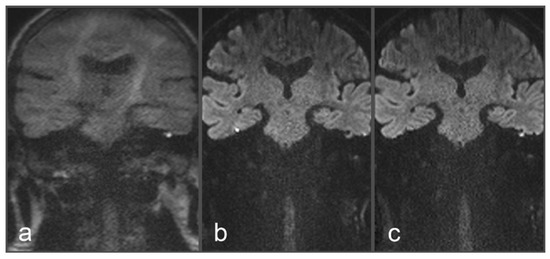

Figure 2. Images of a 48-year-old patient with a suspected cholesteatoma on the left side. (a) tseDWI. (b) uncorrected rsDWI. (c) topup-corrected rsDWI (each sample image in coronal slice orientation). Both tseDWI and topup-corrected rsDWI show a small hyperintense lesion in the upper middle ear on the left side, which could be confirmed as a cholesteatoma after surgery and histopathological examination. In contrast, uncorrected rsDWI was not able to delineate the cholesteatoma on the left side with comparable hyperintense signal intensity and shows a strong geometrical distortion of the lesion. Additionally, uncorrected rsDWI demonstrates two additional lesions: punctual on the left lateral side and brightly appearing on the right side; both were valued as artifacts due to their absence in tseDWI and topup-corrected rsDWI, respectively.